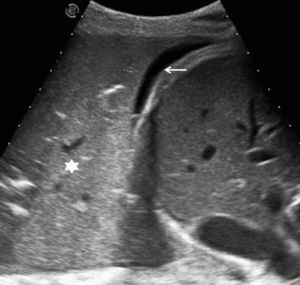

El aspecto ecográfico de un derrame pleural depende de su naturaleza, causa y cronicidad. Por sus características ecográficas los derrames pueden dividirse según presenten ecos internos, septos (gruesos o finos y móviles) y/o nodularidad pleural, o sean totalmente anecogénicos. Se ha demostrado que la ecografía es más sensible que la TC para demostrar la existencia de septos (fig. 1) en el interior de un derrame pleural4,18. La presencia de ecos, septos o nódulos permite catalogarlo de exudado19. La ausencia de estos hallazgos, es decir, el hecho de que se trate de un líquido anecogénico, no permite determinar que sea un trasudado, dado que los exudados se pueden presentar de esta manera19.

En pacientes de difícil movilización, como los ingresados en unidades de cuidados intensivos, la ecografía también es útil para determinar si las alteraciones visibles en la radiografía anteroposterior en decúbito supino corresponden a derrame pleural o a consolidaciones parenquimatosas (fig. 2). Además, como se comenta más adelante, también permite la obtención de líquido pleural de forma rápida y segura.